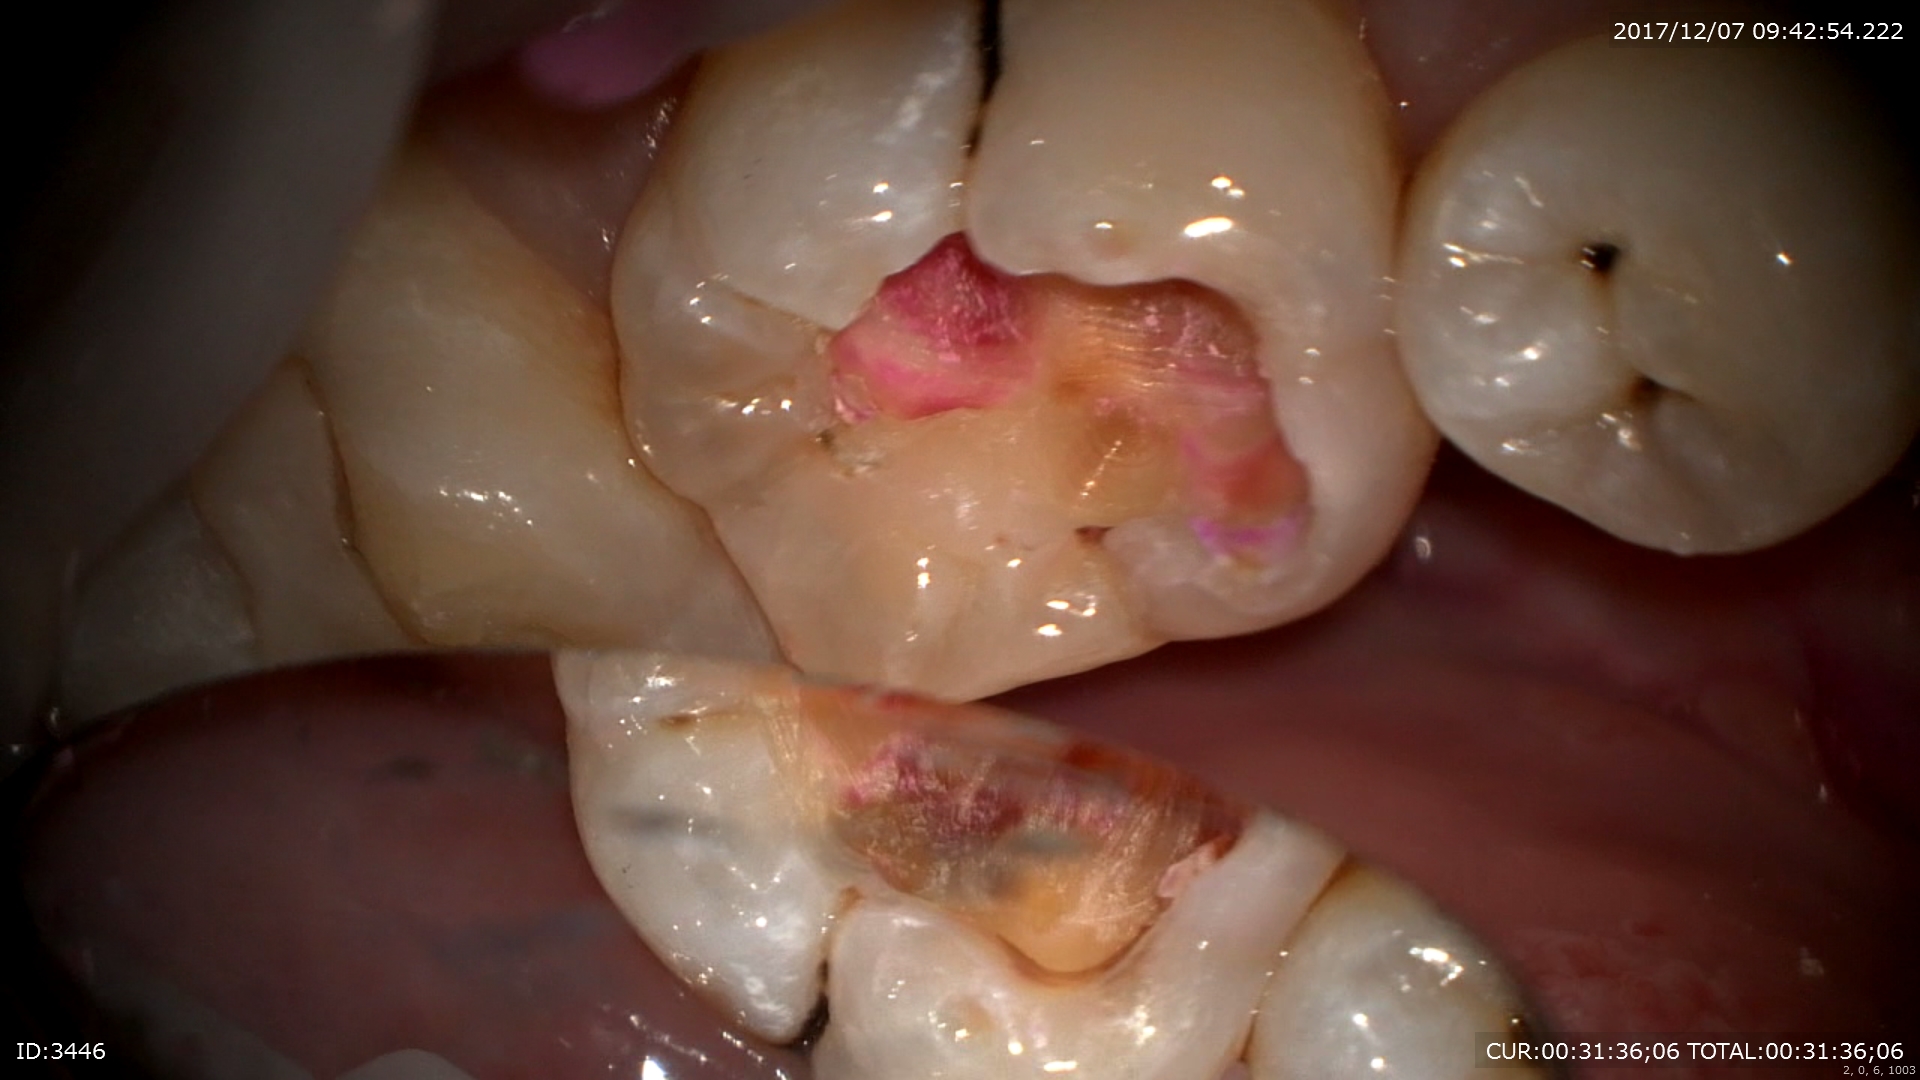

2ケース目:銀歯虫歯。私はこの銀歯治療は行いませんが、この銀歯を行わない理由がここにあります。銀歯が腐食していますね。

中は

こんな感じ